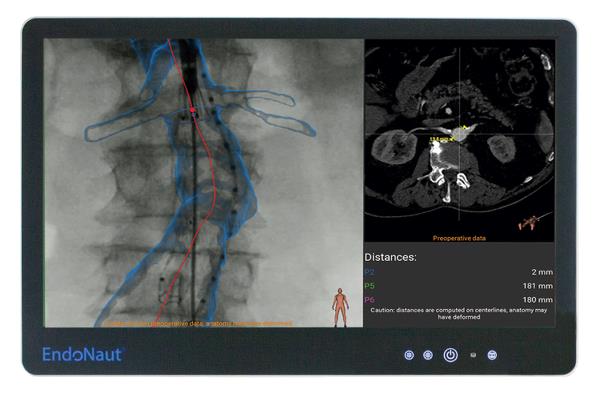

EndoNaut er et intraoperativt 3D-navigationssystem til endovaskulær behandling af aneurismer og stenoser. Den patenterede løsning til 3D-navigation giver dig visuel støtte under operationen og hjælper dig til at udføre indgrebet med stor nøjagtighed og selvsikkerhed. EndoNaut kan let integreres på din operations- eller interventionsstue. Uanset fabrikat.

EndoNaut er et omkostningseffektivt alternativ til en hybrid operationsstue. Udover 3D-billedfusion til aorto-iliaca procedurer giver EndoNaut dig en navigationsløsning til PAD-behandling, der er kompatibel med enhver mobil eller fast C-bue.